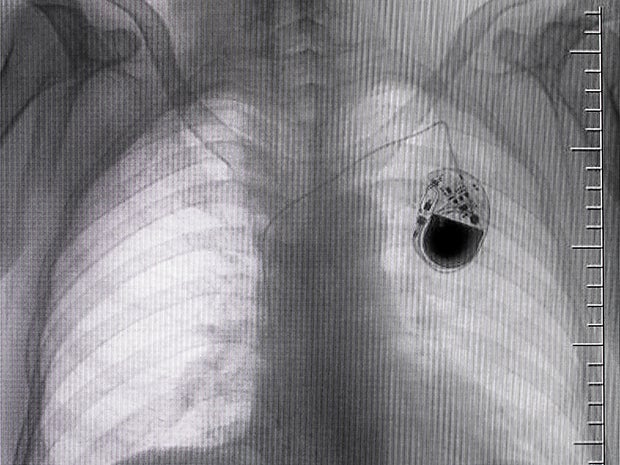

Radiology is the science of high-energy radiation for the diagnosis and treatment of disease. Teleradiology extends this definition into the transmission of radiological patient images — X-rays, CT scans and MRIs, for example.

- Computed tomography (CT scan): CT scans use X-rays combined with computing algorithms to create an image of the body. Often used for urgent or emergent conditions including cerebral hemorrhage, pulmonary embolism (clots in the arteries of the lungs), aortic dissection (tearing of the aortic wall) and obstructing kidney stones.

Teleradiology is the transmission of radiographic images from one location to another for sharing studies with other radiologists and physicians. The benefits of teleradiology mirror the benefits of telehealth. A doctor who needs the results of a scan can transmit that image to the West Coast or overseas to ensure a timely reading.

The primary benefit of blockchain technologies, when applied to teleradiology, is “truth,” not “trust” by offering an integrity check on patient images. Yesterday, radiologists had to trust that images were accurate and unaltered — but they had no proof. Today, they have truth — immutable evidence that the images they are reading are unchanged.

Truth over the trust is the business care for teleradiology — patient image proof for treatment and diagnosis.